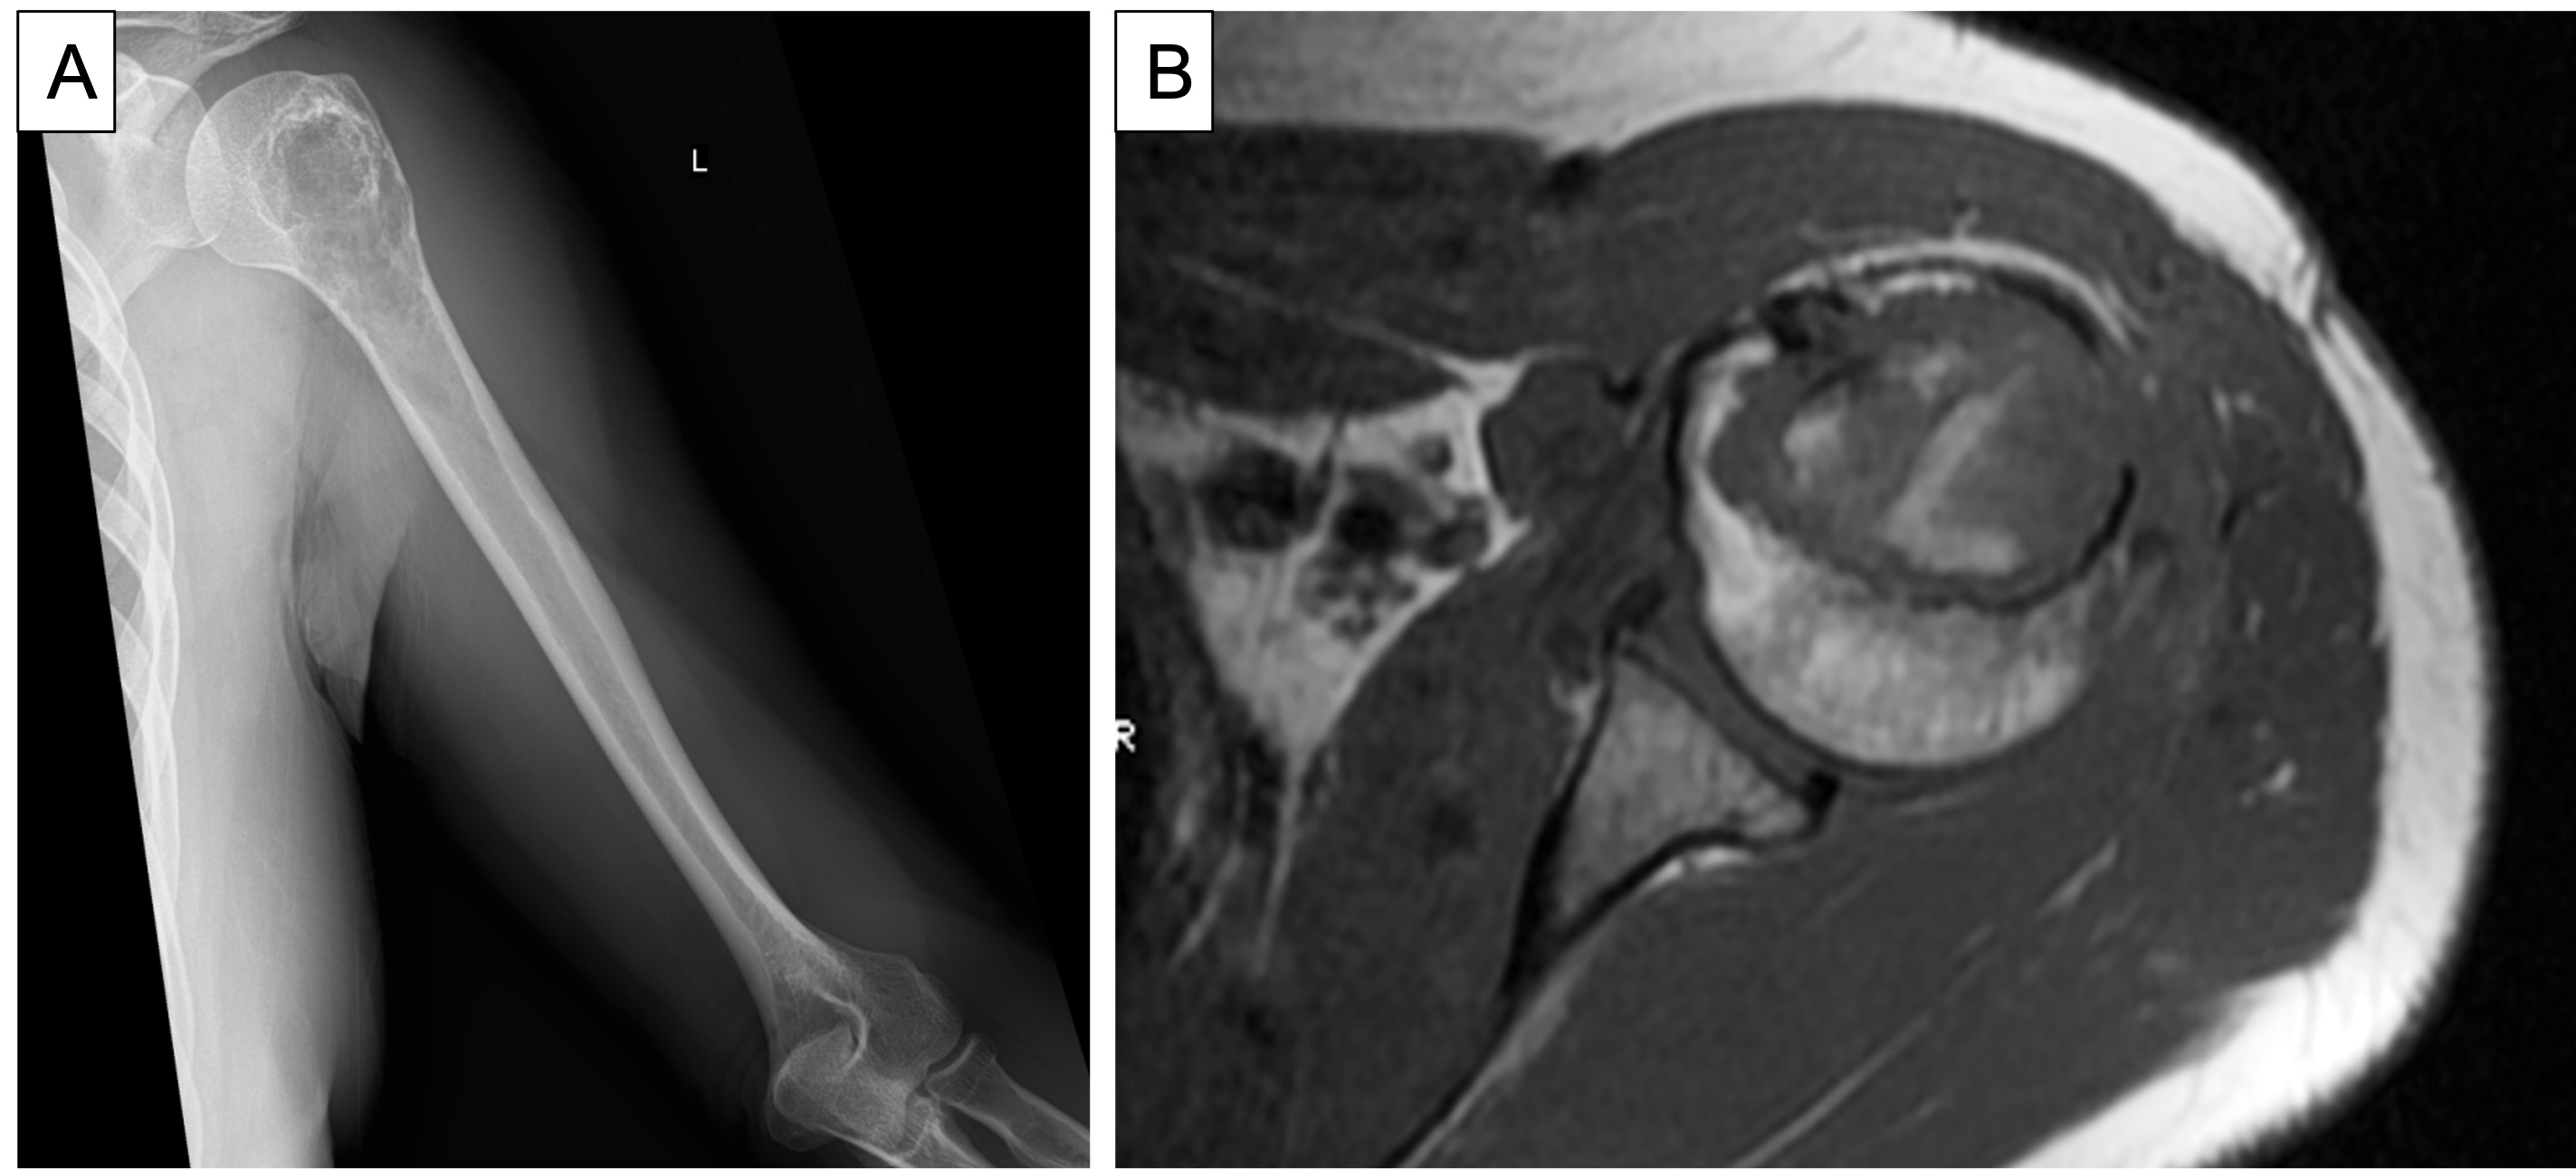

Radiology description

- Radiographically, it appears as an ill defined lytic lesion with geographical destruction, cortical scalloping and thickening of the cortex, often containing popcorn calcifications (Eur J Radiol 2015;84:2222)

- MRI shows lesions > 2 cm with cortical remodeling, deep scalloping and enhancement

- MRI is the best validated method to detect an atypical cartilaginous tumor arising in an osteochondroma

- Cartilaginous cap thickness of > 2 cm in osteochondroma may raise concern for malignant transformation but is not entirely sufficient (Rofo 2021;193:262)

- Presence of cortical expansion, followed by the presence of deep endosteal scalloping and a size > 6 cm, is the key imaging feature for differentiating enchondroma from atypical cartilaginous tumor, on both CT and MRI (Acta Radiol 2022;63:376)

Radiology images

Practice question #1

A 41 year old woman complained of an enlarging mass at her left proximal humerus. Xrays showed a lucent lesion with indistinct borders and endosteal scalloping. MRI showed an irregular, expansile, avidly enhancing mass. A biopsy of the lesion was performed and is shown above. What is the diagnosis?